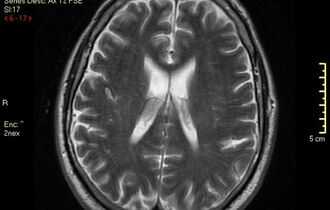

МРТ головного мозга. Т2-взвешенная МРТ типа FLAIR . Множественные туберкулемы.

ВИЧ-инфекция особенно способствует развитию туберкулеза. При нейротуберкулезе при МРТ головного мозга наблюдаются менингиты, гидроцефалия, инфаркты в бассейне СМА и стволе мозга, возможно развитие церебрита, абсцесса и формирование туберкулем. Туберкулемы при МРТ головного мозга представлены очаговыми поражениями, количество которых варьирует от одного до нескольких или множественные. Туберкулезные очаги обычно окружены перифокальным отеком, который может быть минимальным. МРТ-картина зависит от зрелости туберкулемы. На МРТ головного мозга неказеозная туберкулема имеет гипоинтенсивный МРТ-сигнал на Т1-ВИ и гиперинтенсивный МРТ-на Т2-ВИ. Постконтрастные МРТ изображения характеризуются гомогенным усилением. Казеозная туберкулема с жидким центром визуализируется как гиподенсное образование с кольцевидным постконтрастным усилением. При МРТ отмечается стандартное изменение сигнала, а после внутривенного контрастирования-кольцевидное усиление. Казеозная туберкулема на Т2-ВИ МРТ головного мозга характеризуется изо-или гипоинтенсивным сигналом. Внутривенное контрастирование при МРТ головного мозга позволяет проследить связь с измененными оболочками мозга.